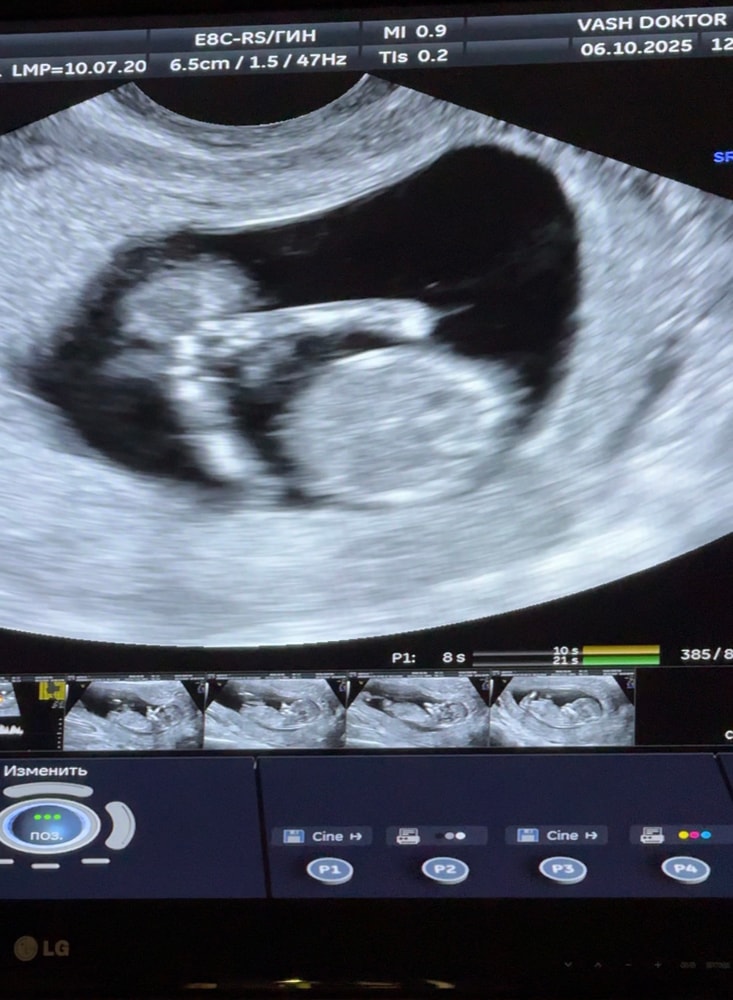

Анализы, скринингиСегодня был 1й Скрининг - всё хорошо, мы здоровы по генетике)

Малыш догнал свой срок по М - 12+4 (была поздняя О, 5 дней опоздания)

КТР - 6,1 см

ТВП - 1,6

СБ - 165 уд/мин

Носовая кость есть, все пучком)

P.S. - в 12 часов дня человек спал😂 узист потыкала его датчиком в живот, он только сделал потягуси и дальше спать лег😂😂

на фото как раз закрылся ручками и дрых)